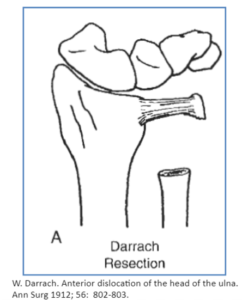

Şiddetli veya çoklu TFCC yırtığı vakalarında cerrahın yaralanmayı metal çiviler, vidalar veya diğer sabitleme cihazlarıyla onarması gerekebilir. Bu daha yoğun cerrahi tedavi için açık bir kesi gerekir. Ulnar varyans varsa, cerrahın bunu kısaltmak için açık ameliyata ihtiyacı olabilir. Bu yaralanma için açık cerrahi teknikler şunları içerir:

- Darrah

- Tenodezli Darrach

- Hemireksiyon-İnterpozisyon

- Sauve-Kapanji

- Ulna Başı Değişimi